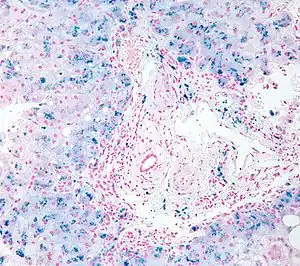

| Micrograph of liver biopsy showing iron deposits due to haemosiderosis. Iron stain. | |

In general, the term hemosiderosis is used to indicate the pathological effect of iron accumulation in any given organ, which mainly occurs in the form of the iron-storage complex hemosiderin.[16][17] Sometimes, the simpler term siderosis is used instead.

Biopsy

Liver biopsy is the removal of small sample in order to be studied and can determine the cause of inflammation or cirrhosis. In someone with negative HFE gene testing, elevated iron status for no other obvious reason, and family history of liver disease, additional evaluation of liver iron concentration is indicated. In this case, diagnosis of hemochromatosis is based on biochemical analysis and histologic examination of a liver biopsy. Assessment of the hepatic iron index (HII) is considered the "gold standard" for diagnosis of hemochromatosis.